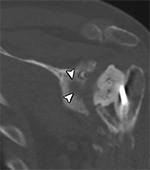

Scaphoid Fracture Evaluation. (A) Sagittal multiplanar reformation shows central portion of compression screw in the scaphoid with incomplete union at periphery of fracture site (arrowheads). Note absence of streak artifact due to small size of screw. (B) Coronal multiplanar reformation shows fracture union at the central portion of the scaphoid waist, indicating partial union.